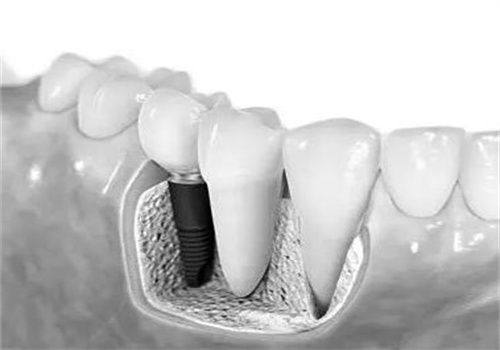

种植牙是合肥美奥口腔医院的特色项目之一。医院拥有精良的种植牙设备和技术,能够为患者提供高质量的种植牙服务。在种植牙过程中,医生会根据患者的口腔情况和身体状况,选择更适合的种植体,确保种植牙的成功几率和使用寿命。说到种植牙,就不得不提到合肥美奥口腔医院的陈国庆医生。陈医生是医院的从业多年种植骨干医生,他拥有多年的种植牙临床经验,擅长各种复杂的种植牙手术。他对待每一位患者都非常认真负责,会耐心地为患者解答疑问,制定更适合的治疗方案。在他的努力下,许多患者都成功地拥有了健康的牙齿。